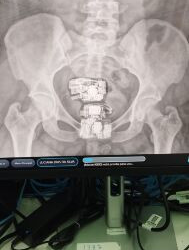

Mulher esconde 2 celulares, 4 carregadores e 8 cabos USB no corpo para entregar a preso

DivulgaçãoRaio X flagrou a visitante com vários materiais escondidos na região genital DivulgaçãoRaio X flagrou a visitante com vários materiais ...